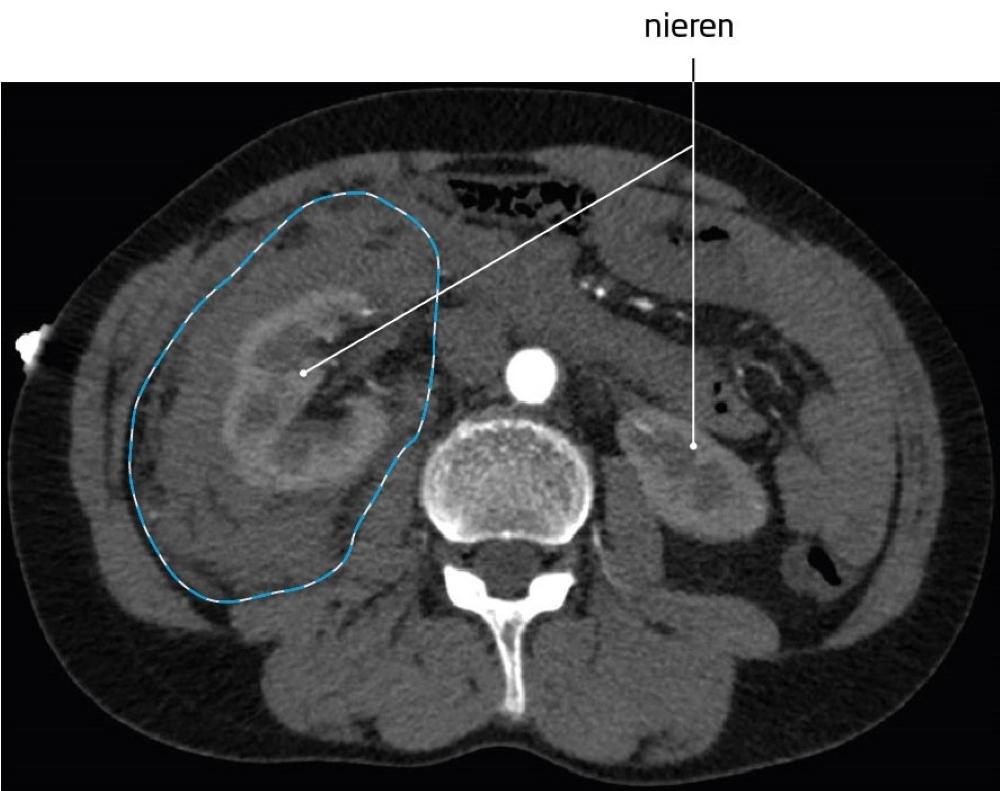

Gepubliceerd: Week 15 - 2024 1096 deelnemers Een 74-jarige vrouw komt op de spoedeisende hulp met livide verkleuring in de rechterflank en een Hb-waarde van 4,7 mmol/l. Je vermoedt een retroperitoneale bloeding. Welke klacht komt het meest voor bij een retroperitoneaal hematoom? Antwoord Pijn in de buik, die kan uitstralen naar rug of been. Een palpabele zwelling in de buik. Huidverkleuring van buik, rug of flank. Een daling van de bloeddruk. Antwoord controleren